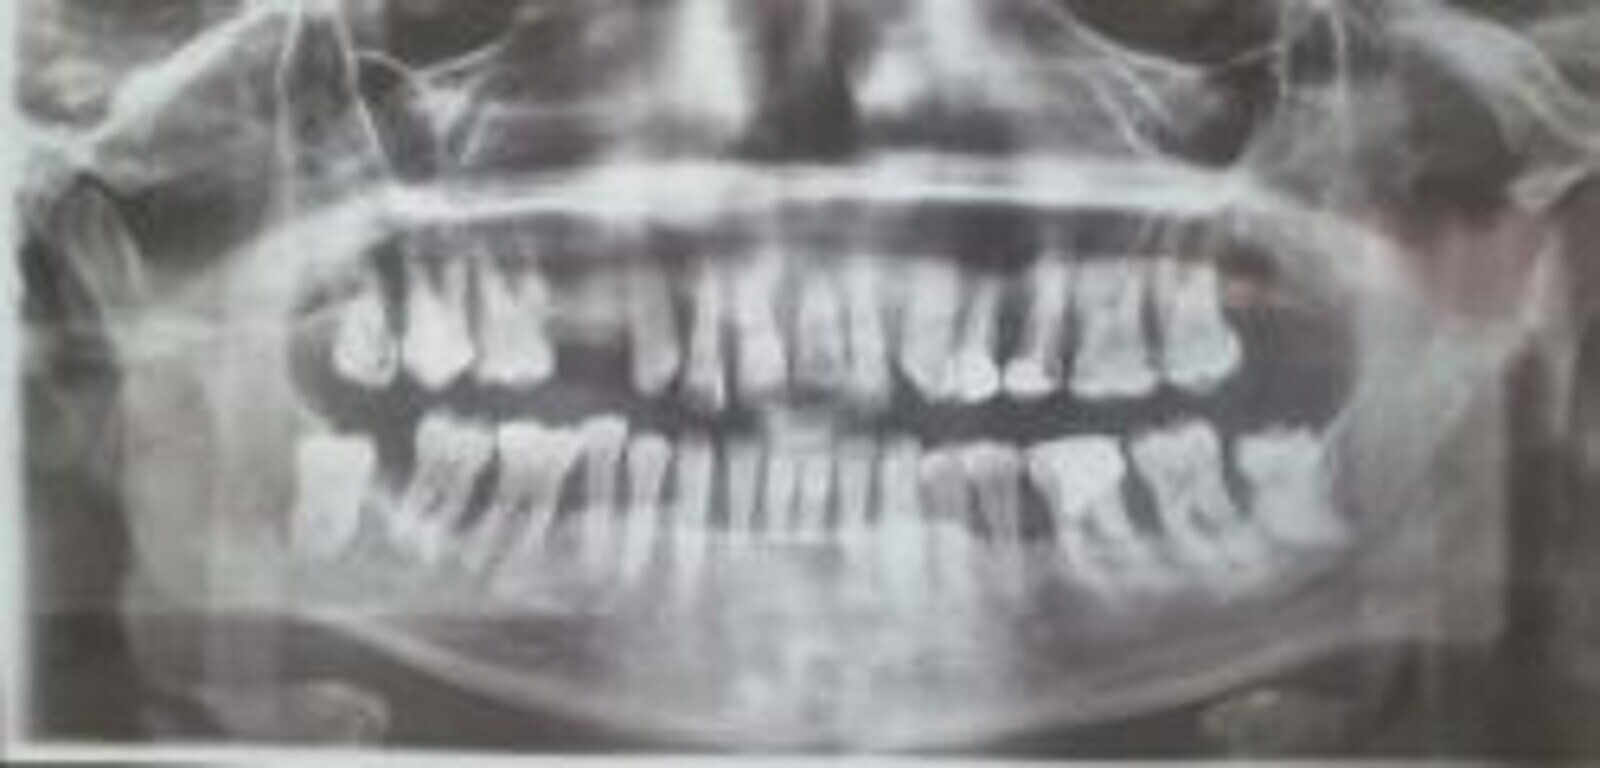

perte osseuse objectivable sur la radiographie [Fig 2 ,3]

Fig. 3 : Radiographie panoramique de la même patiente qui objective les lyses osseuses généralisées.